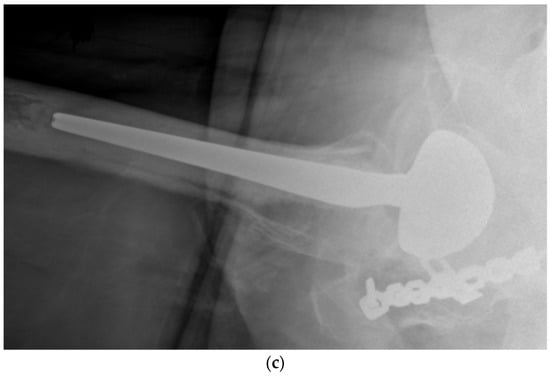

Using a LDH THA allows unrestricted movement after THA for all types of surgical approaches. Vendittoli’s group in Canada practices no postoperative ROM restriction for the posterior surgical approach, as it simplifies patients’ education, enhances their confidence during rehabilitation, and facilitates bilateral procedures [,]. LDH monobloc DM is especially interesting for many older women with large femurs and a small acetabular cavity (<50 mm, Figure 7). In these cases, using a standard bearing diameter is prone to instability. With its LDH, DM design provides optimal implant stability for these not so infrequent patients. Moreover, with LDH, we do not impose activity restrictions in the long term. LDH CoC THA offers a significant benefit for many active individuals who can return to their regular jobs and for those who want to practice demanding sporting activities.

Figure 7.

(a) Antero-posterior pelvis radiograph of a 75-year-old woman with severe bilateral hip osteoarthritis. During the right THA surgery, the acetabular cavity was reamed to 47 mm. A monobloc acetabular component of 48 mm was implanted with a DM polyethylene head of 41 mm (28 mm metal head). A polished tapered stem was cemented. (b) Post-operative anteroposterior pelvis radiograph.